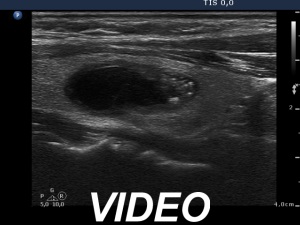

Ultrasonography. The thyroid was echonormal. There was a minimally-moderately hypoechogenic nodule in the right while a cystic nodule in the left lobe. There were numerous hyperechogenic figures both in the cystic and in the lower solid part of the lesion. The lesion presented no vascularization.

Comment. The presentation of the bright hyperechogenic granules are relatively unusual, they were mostly located within the solid part causing a false impression of starry sky phenomenon. In fact, they were comet-tail artifacts.